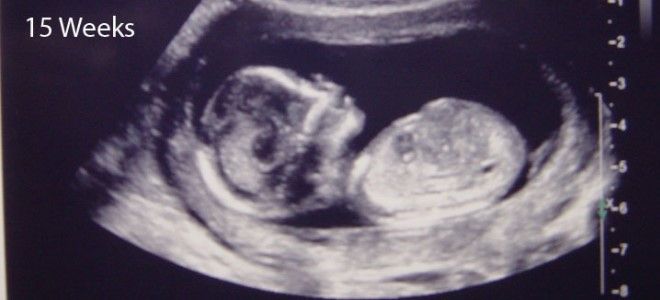

УЗИ плода на 15 неделе беременности

УЗИ – один из самый информативных методов для определения параметров развития плода. Его часто назначает гинеколог, если возникают сомнения в благополучном течении беременности. Врач с помощью ультразвукового аппарата может рассказать матери и отцу, каковы самочувствие малыша и окружающая его среда. Фото на 15 неделе беременности покажет размер и массу тела ребенка, количество околоплодных вод, состояние плаценты. Если предлежание ребенка позволяет увидеть половые органы, некоторые специалисты называют пол плода.

Такой вид обследования необходим для ясной картины состояния жизнедеятельности плода. В 15 недель можно уже разглядеть половые органы малыша и понять кто появится на свет через несколько месяцев. Если повезет, то на УЗИ можно увидеть активные шевеления малыша, как он сосет палец или машет ручкой.

С помощью такой аппаратуры можно:

- диагностировать состояние плаценты, околоплодных вод;

- прослушать сердцебиение малыша. Около 140-160 ударов совершает маленькое сердечко, перекачивая около 30 литров крови.

УЗИ безопасный и безболезненный вид исследования.

УЗИ 15 недель беременности

Крайним сроком проведения первого скрининга является конец 13 недели, но не 15 неделя беременности. В ходе этого исследования врачами осуществляется и УЗИ, которое может быть проведено повторно в 15 недель беременности.

В рамках процедуры врач еще раз обращает внимание на пол: на 15 неделе беременности наружные половые органы уже различимы. Однако разглядеть их удается не всегда. Важное значение имеет положение плода во время исследования.